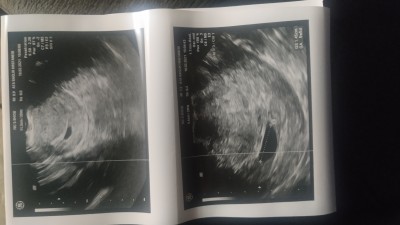

7 haftalik hamileyim dün doktora gittim kese var ama bebeği göremedi acaba küçük diye mi göremedi yoksa boş kese mi on gün sonra bida gidecez

Benimde aynı oldu canım 7. Haftamdayım gittiğimde kesede beklenen büyüklük var ama bebeği göremedim 10 gün sonra bakalım dedi aynı ilaç verdi folukasit kullanıyordum zaten birde düşük önleyici verdi olabilir telaş yapma dedi ama insan yinede merak ediyor

image